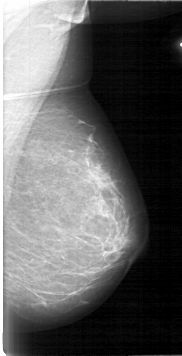

D_4017_1.RIGHT_CC

RIGHT_CC LINES 5296 PIXELS_PER_LINE 2566 BITS_PER_PIXEL 12 RESOLUTION 43.5 OVERLAY